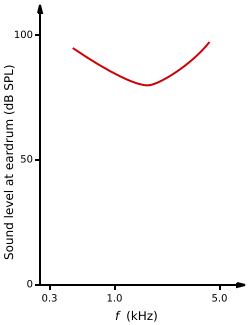

Dead regions affect audiometric results, but perhaps not in the way expected. For example, it may be expected that thresholds would not be obtained at the frequencies within the dead region, but would be obtained at frequencies adjacent to the dead region. Therefore, assuming normal hearing exists around the dead region, it would produce an audiogram that has a dramatically steep slope between the frequency where a threshold is obtained, and the frequency where a threshold cannot be obtained due to the dead region.[15]

However, it appears that this is not the case. Dead regions cannot be clearly found via PTA audiograms. This may be because although the neurons innervating the dead region, cannot react to vibration at their characteristic frequency. If the basilar membrane vibration is large enough, neurons tuned to different characteristic frequencies such as those adjacent to the dead region, will be stimulated due to the spread of excitation. Therefore, a response from the patient at the test frequency will be obtained. This is referred to as “off-place listening”, and is also known as ‘off-frequency listening’. This will lead to a false threshold being found. Thus, it appears a person has better hearing than they actually do, resulting in a dead region being missed. Therefore, using PTA alone, it is impossible to identify the extent of a dead region (See Figure 7 and 8).[15]

Consequently, how much is an audiometric threshold affected by a tone with its frequency within a dead region? This depends on the location of the dead region. Thresholds at low frequency dead regions, are more inaccurate than those at higher frequency dead regions. This has been attributed to the fact that excitation due to vibration of the basilar membrane spreads upwards from the apical regions of the basilar membrane, more than excitation spreads downwards from higher frequency basal regions of the cochlea. This pattern of the spread of excitation is similar to the ‘upward spread of masking’ phenomenon. If the tone is sufficiently loud to produce enough excitation at the normally functioning area of the cochlea, so that it is above that areas threshold. The tone will be detected, due to off-frequency listening which results in a misleading threshold.[15]

To help to overcome the issue of PTA producing inaccurate thresholds within dead regions, masking of the area beyond the dead region that is being stimulated can be used. This means that the threshold of the responding area is sufficiently raised, so that it cannot detect the spread of excitation from the tone. This technique has led to the suggestion that a low frequency dead region may be related to a loss of 40-50 dB.[16][17] However, as one of the aims of PTA is to determine whether or not there is a dead region, it may be difficult to assess which frequencies to mask without the use of other tests.[15]

Based on research it has been suggested that a low frequency dead region may produce a relatively flat loss, or a very gradually sloping loss towards the higher frequencies. As the dead region will be less detectable due to the upward spread of excitation. Whereas, there may be a more obvious steeply sloping loss at high frequencies for a high frequency dead region. Although it is likely that the slope represents the less pronounced downward spread of excitation, rather than accurate thresholds for those frequencies with non-functioning hair cells. Mid-frequency dead regions, with a small range, appear to have less effect on the patient's ability to hear in everyday life, and may produce a notch in the PTA thresholds.[15] Although it is clear that PTA is not the best test to identify a dead region.[18]